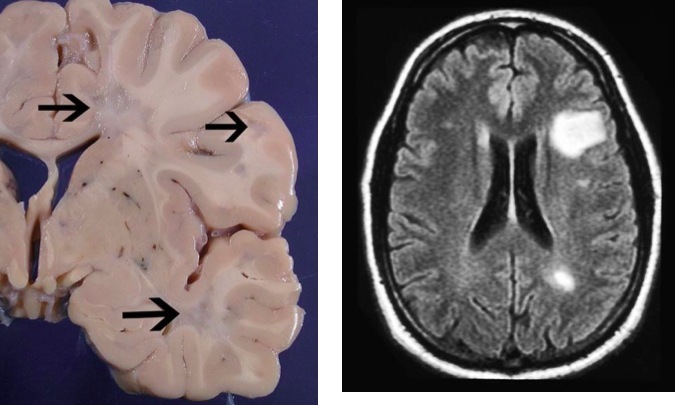

Multiple Sclerosis

– common, young adults, F:M = 3:1, latitude

– Other associations: smoking, low vitamin D, maternal history

MRI: demyelination plaques

Pathology

– perivascular lymphocytic inflammation

– demyelination (patchy loss of myelin): grey & white matter *

– symptoms related to area involved & gray matter injury may correlate best with disability*